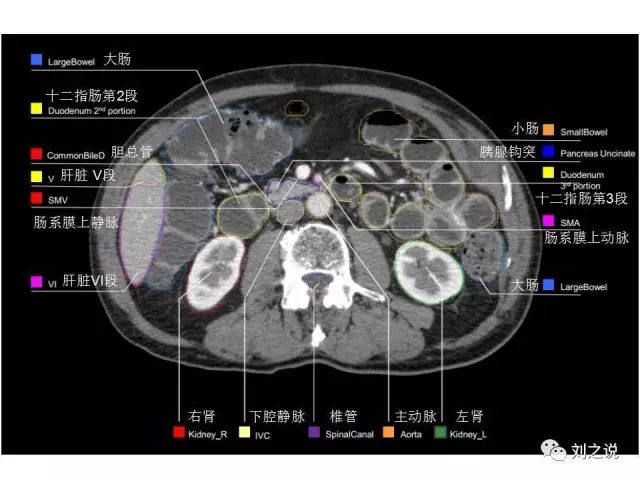

【解剖】高清实用 腹部CT断层

参考RTOG共识和3D-body解剖。